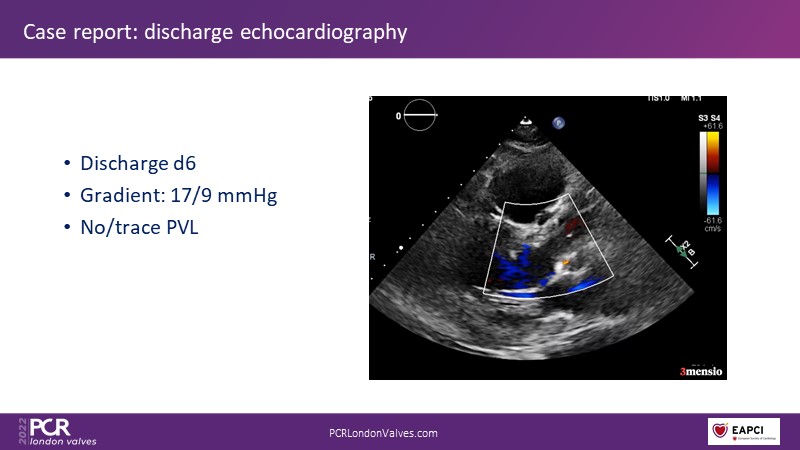

- To learn how paravalvular leakage may impact on patient outcomes